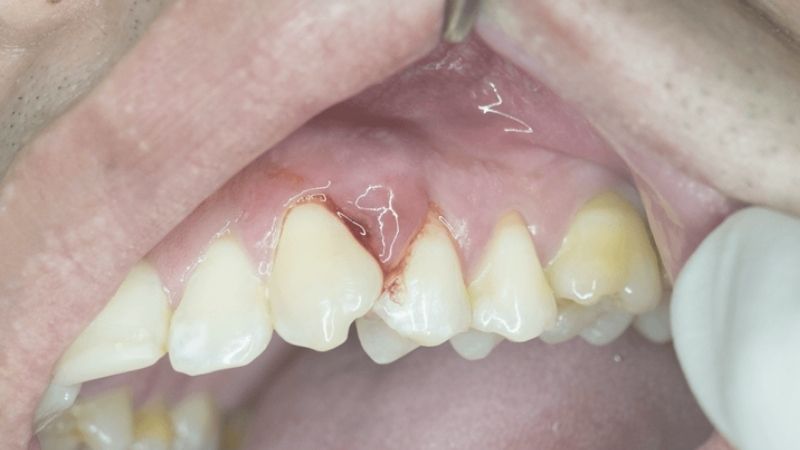

2. Sưng tấy vùng má hoặc nướu

Khu vực quanh răng bị áp xe thường sưng đỏ, có thể nhìn thấy một hoặc nhiều ổ mủ nhỏ màu trắng hoặc vàng.